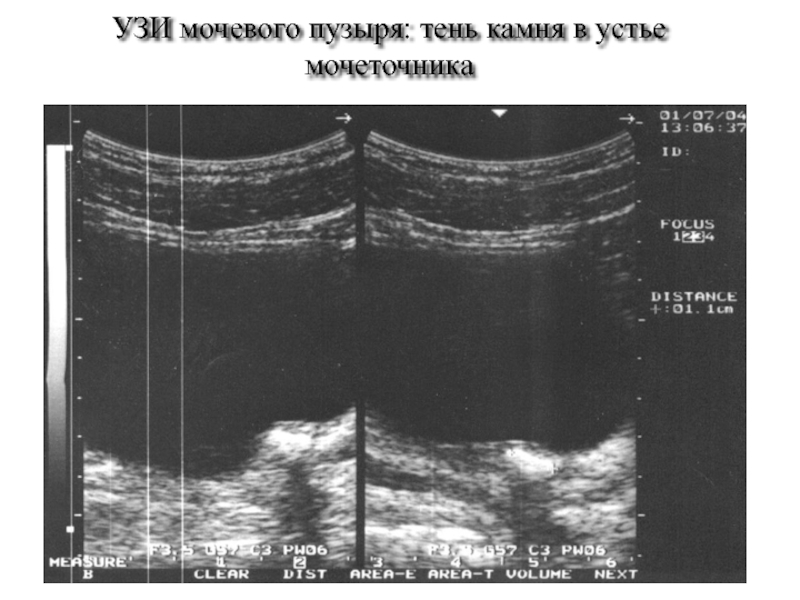

Слайд 63УЗИ мочевого пузыря: тень камня в устье мочеточника